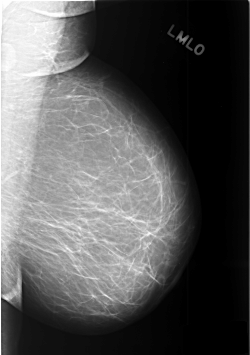

C_0446_1.LEFT_MLO

C_0446_1.LEFT_CC

LEFT_MLO LINES 5680 PIXELS_PER_LINE 3992 BITS_PER_PIXEL 12 RESOLUTION 50 NON_OVERLAY